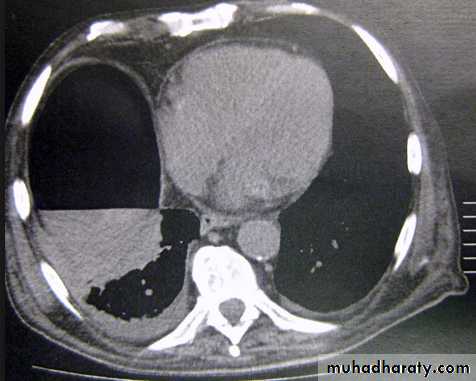

Pleural Effusion on Chest Radiographs.

Posteroanterior (A) and lateral (B) chest radiographs demonstrate the typical meniscoid appearance (arrows) in a patient with a left pleural effusionHydropneumothorax.